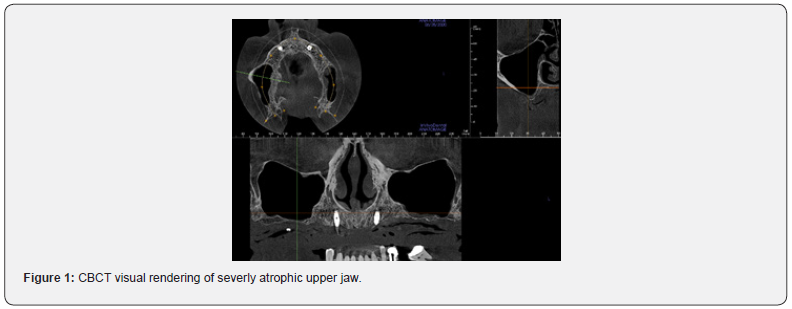

The radiological template undergoes a CB-CT exam alone. Once radiological examination’s correctness is verified, both DICOM files series obtained are unified to achieve a digital reconstruction of the upper jaw and its occlusal relation with lower one (Figure 1). Next phase is characterized by sub-periosteal implant digital design starting from occlusion and positioning future prosthetic prominences into their final positions. Implant fixing screws positions are then determined to assure a correct bone rigid fixation, starting from facial buttresses lines, in particular respecting nasal-maxillary and zygomatic-maxillary ones: in fact, canine fossa and zygomatic bone displays ideal thicknesses (6- 8mm) to allow synthesis screw’s stable fixation (Figure 2) [5]. Designing phase ends with surgeon’s project validation and subperiosteal implant production [6,7]: this process is conducted by “laser melting technique” (homogeneous layers of titanium powders are fused together in an additive way by a laser beam, following the 3D virtual model), employing grade V Titanium alloy (Ti-6-Al-4V). Then, the structure is electropolished and decontaminated, before sterilization. Together with the subperiosteal implant, a stereolithographic and autoclavable clone model of the structure is provided (Figure 4).